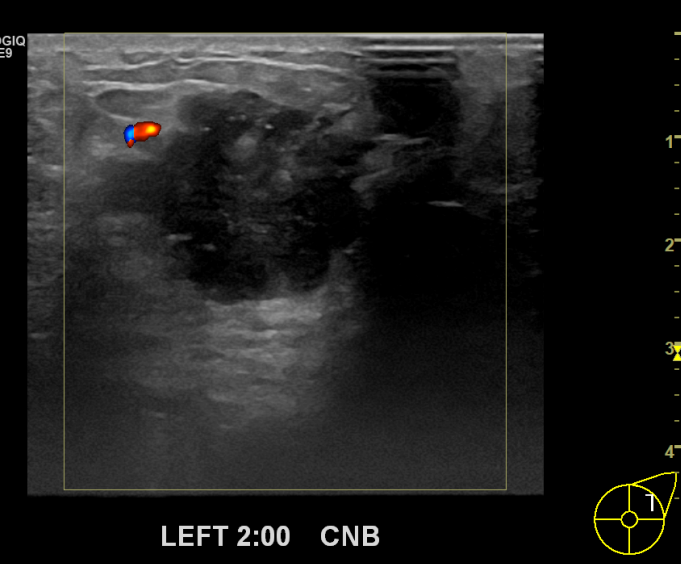

상기환자 좌측만져지는 멍울로 내원하신 50대 여성분으로

좌측 조직검사 시행해 침윤성암으로 진단되었습니다.